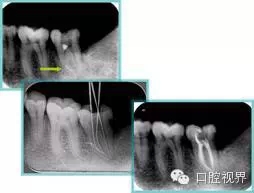

6. 術(shù)后 X 線片

術(shù)后 X 線片用來評定根管充填 長度、致密度(管壁清晰、側(cè)枝)等指標(biāo)。

左圖為根管充填術(shù)后 X 線片。圖中可見,根管充填較好。右下圖有白色小點(diǎn),為側(cè)方加壓導(dǎo)致糊劑擠出所致,表明根管充填比較致密。

致密、恰到好處的充填可去除干凈根管里感染灶,機(jī)體逐漸恢復(fù)。

多根牙時(shí)候需進(jìn)行偏移投照,正位投照無法說明具體哪根牙根管充填效果。